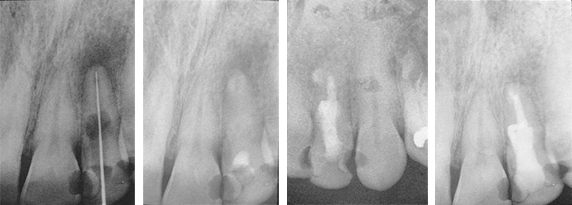

Treatment of Periapical Lesion and Internal Resorption

The patient presented with considerable discomfort and extreme sensitivity to hot, cold and percussion.

Fig. 1: Diagnostic radiograph shows internal resorption and periapical lesion of the maxillary left lateral. TempCanal was placed at this visit (not shown).

Fig. 2: Radiograph taken 3 months later shows TempCanal in place and periapical healing occurring.

Fig. 3: Radiograph taken after 13 months shows the root canal obturated with Pulpdent Root Canal Sealer using the Pulpdent Pressure Syringe. Note the slight extrusion of sealer beyond the apex and the internal resorption space obturated with sealer.

Fig. 4: Radiograph taken after 19 months shows internal resorption controlled and periapical lesion healed. Note lamina dura. Also shows a portion of the root canal sealer removed and the entire tooth reinforced with Pulpdent HardCord dual cure composite restorative using DenTASTIC as the bonding adhesive.

Treatment of Persistent Periapical Lesion

The Patient had been under treatment for 4 years for a persistent periapical lesion with constant drainage of his left central incisor. Retrograde surgery for removal of the cyst was scheduled. As a temporary measure before surgery, the pulp was removed and TempCanal was placed in the canal. The maxillary left lateral also tested non-vital and was endodontically treated and obturated with Pulpdent Root Canal Sealer at the same visit.

Fig. 1: Radiograph shows periapical lesion involving the maxillary left central and lateral incisors.

Fig. 2: Six weeks following the placement of TempCanal, radiograph shows trabeculation occurring in the periapical area. The surgical procedure was postponed, the TempCanal dressing was changed, and the case was followed until healing of the periapical lesion occurred.

Fig. 3: One year follow up shows healing without surgery and final obturation with Pulpdent Root Canal Sealer using the Pressure Syringe technique.